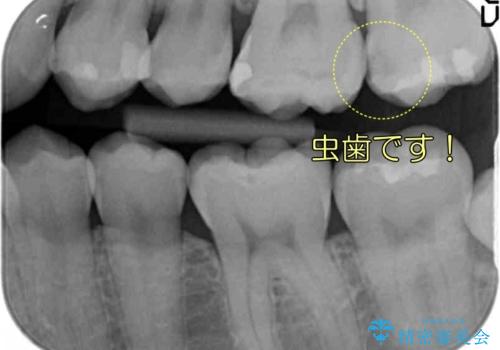

全体矯正をする前の虫歯チェックで見つかった虫歯です。

奥歯の虫歯治療でしたが、プラスチック周りと、歯と歯の間が大きな虫歯になっていました。

インレーでの修復予定でしたが、歯と歯の間が狭く、正確な型取りが難しい状態でした。